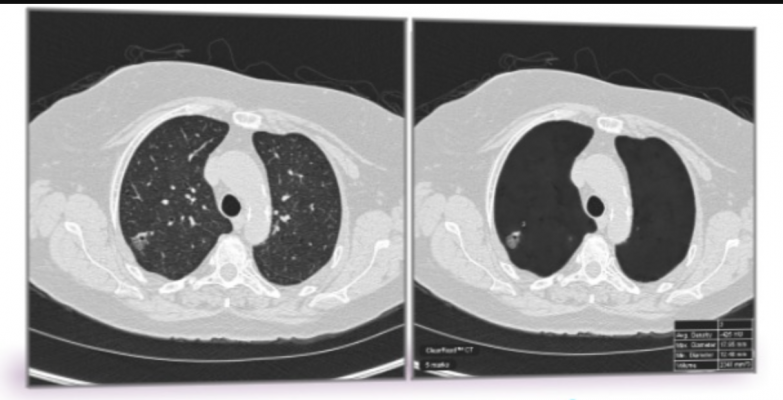

Asbestosis sometimes called white lung occurs as a result of long term or heavy exposure to asbestos fibersindividualsoften workersinhale these fibers which cause damage to the lungs over time. Advanced lung cancer means the cancer has spread from the lung to somewhere else in the body. The superior vena cava is a large vein in the chest.